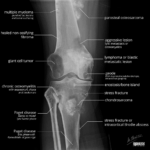

[doctormodu]1 knee bone lesions

03 무릎뼈질환 감별해야할것